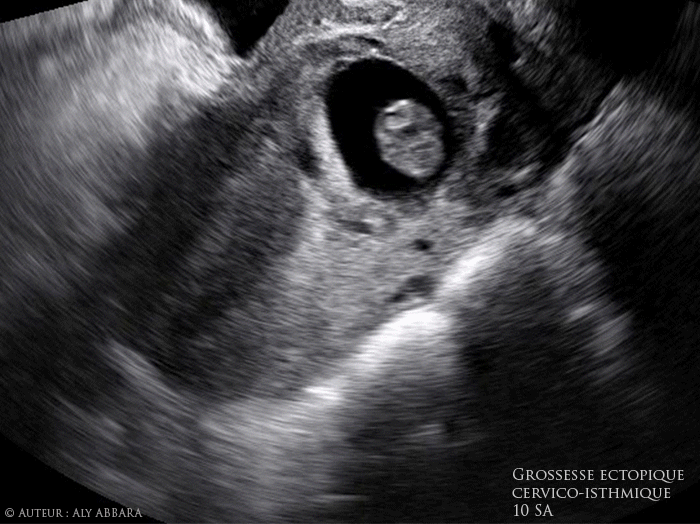

Grossesse évolutive extra-utérine cervico-isthmique intra-murale antérieure (au niveau de l'ancienne cicatrice de césarienne) évolutive de 10 SA

• Séquences de vidéos et d'images échographiques par voie endovaginale mettant en évidence la présence d'une grossesse évolutive extra-utérine cervico-isthmique intra-murale antérieure (au niveau de l'ancienne cicatrice de césarienne) de 10 SA.

Ce sac gestationnel est composé :

• D'un sac gestationnel circonscrite par une couronne trophoblastique en contact direct, en avant, avec la paroi vésicale postérieure.

• D'un foetus mesurant 30,3 mm de longueur crânio-caudale (LCC) et correspondant à une grossesse de 10 SA, évolutive (activité cardiaque et mouvements actifs fœtaux sont présents).

• Cette grossesse est survenue chez une femme âgée de 30 ans, troisième geste, ayant dans ses antécédents deux accouchements par césarienne.

• Elle se présente aux urgences suite à la survenue de métrorragie de très faible abondance après 10 semaines d'aménorrhée.

• L'examen clinique montre la présence d'une légère métrorragie provenant du canal endocervical, avec utérus augmenté de volume (environ 10 SA de taille) et col fermé.

• Le dosage de β-hCG plasmatique = 57 000UI/L